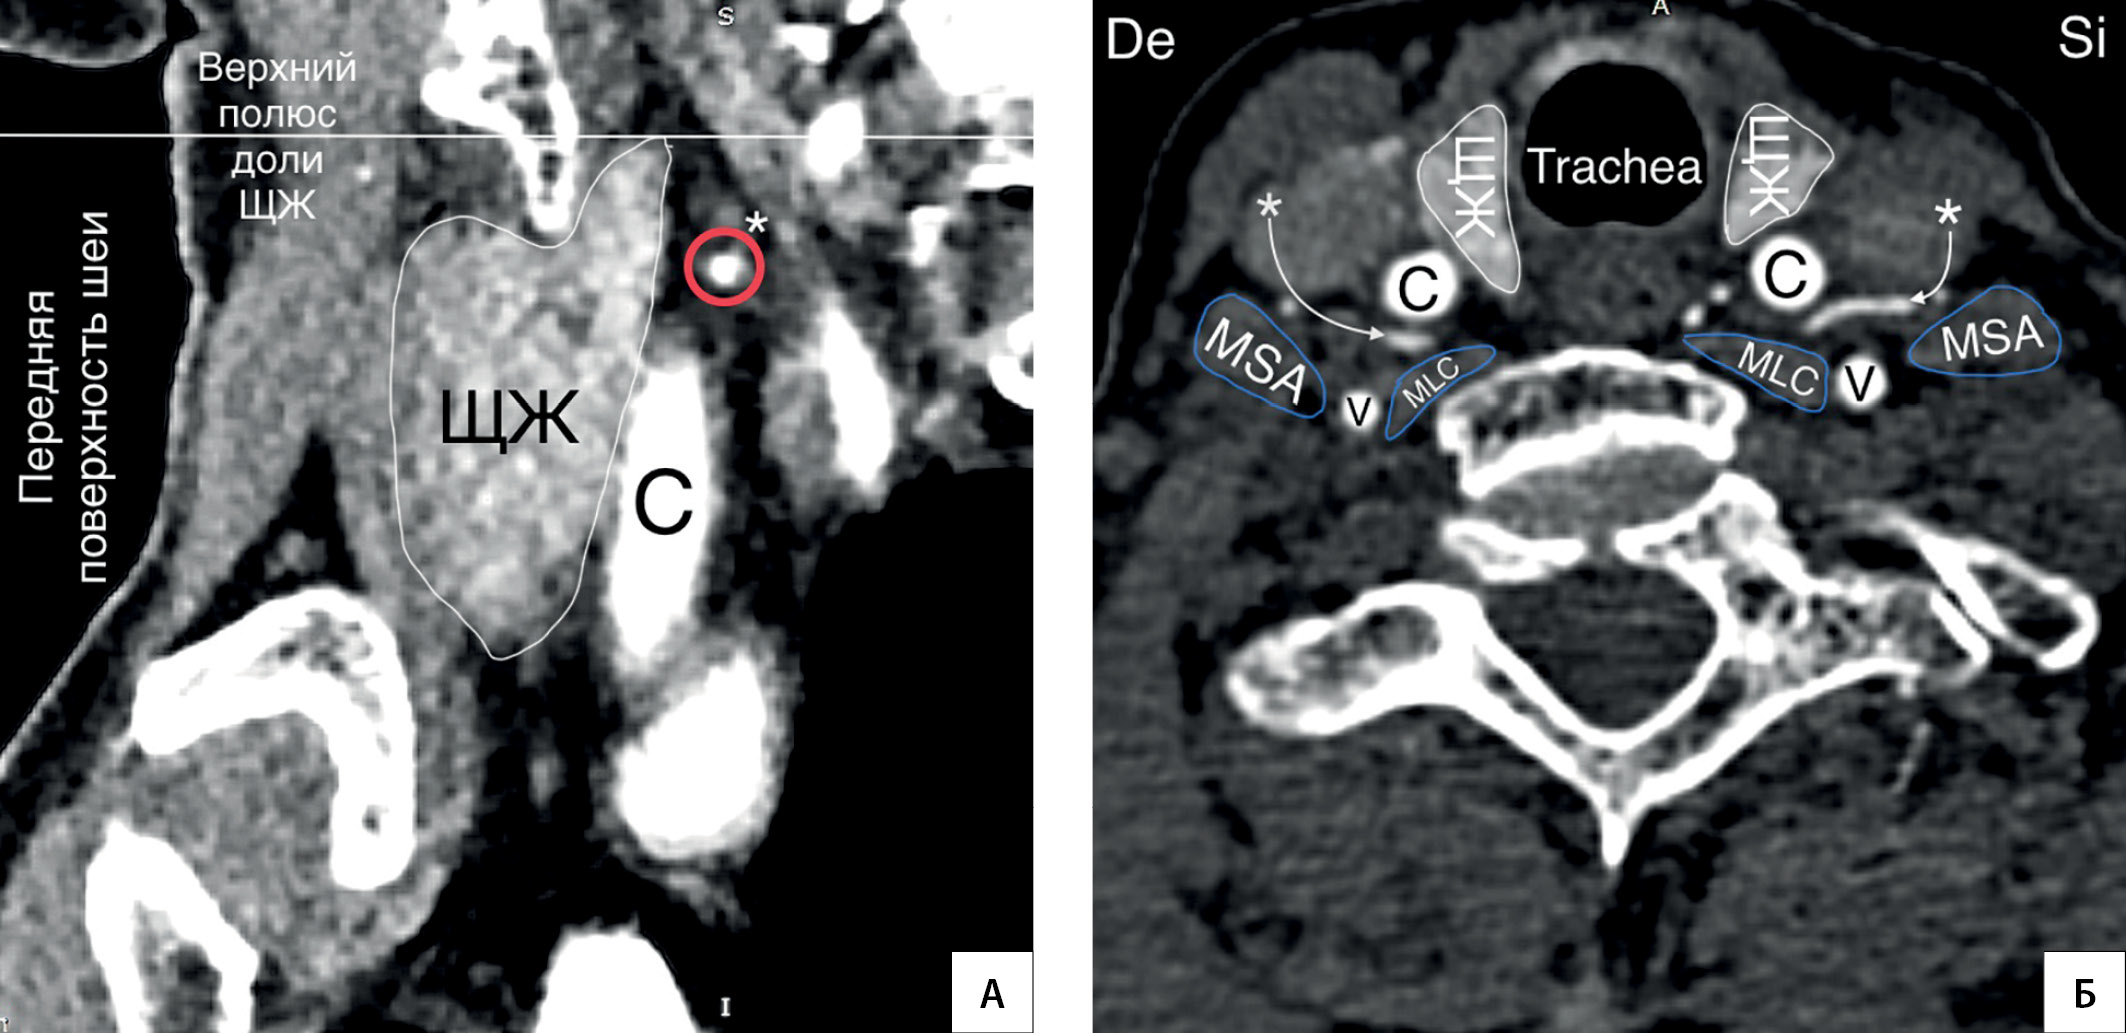

4. Рисунок 4. Колено НЩА располагается на уровне верхнего полюса доли ЩЖ. А — КТ-ангиограмма (фронтальный срез); Б — КТ-ангиограмма (горизонтальная плоскость); * — колено НЩА. C — a. carotis communis; V — a. vertebralis; MSA — musculus scalenus anterior; MLC — musculus longus colli; De — dextra; Si — sinistra. | |